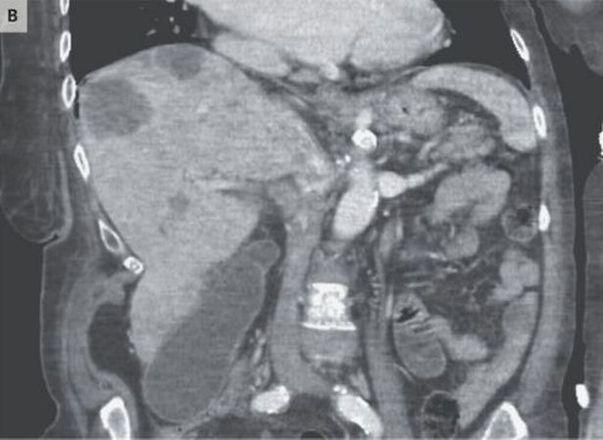

Testes de amostras de cocô e outros exames revelaram que o câncer se espalhou do cólon para o fígado, e seu tratamento seria apenas paliativo